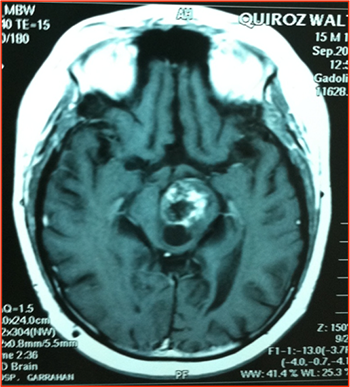

Figura 2: IRMN T1. Imagen atípica en tumor difuso de protuberancia. Con gadolinio tiene un comportamiento no habitual con refuerzo solo en la parte posterior de la misma.

Figura 3: IRMN T1. Tumor en mescencéfalo heterogéneo, dada la alta morbilidad quirúrgica fue realizada una biopsia estereotáctica dando como resultado astrocitoma de bajo grado.